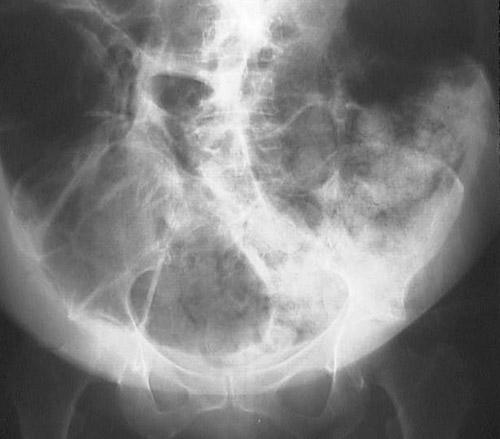

![]() | This attempt at a barium enema has been foiled by a large fecal impaction in which there is a large amount of stool in the colon with irregular areas of opacification. Stool has a granular appearance because the stool is mixed with gas in the colon. Note that the abdomen is quite distended. |